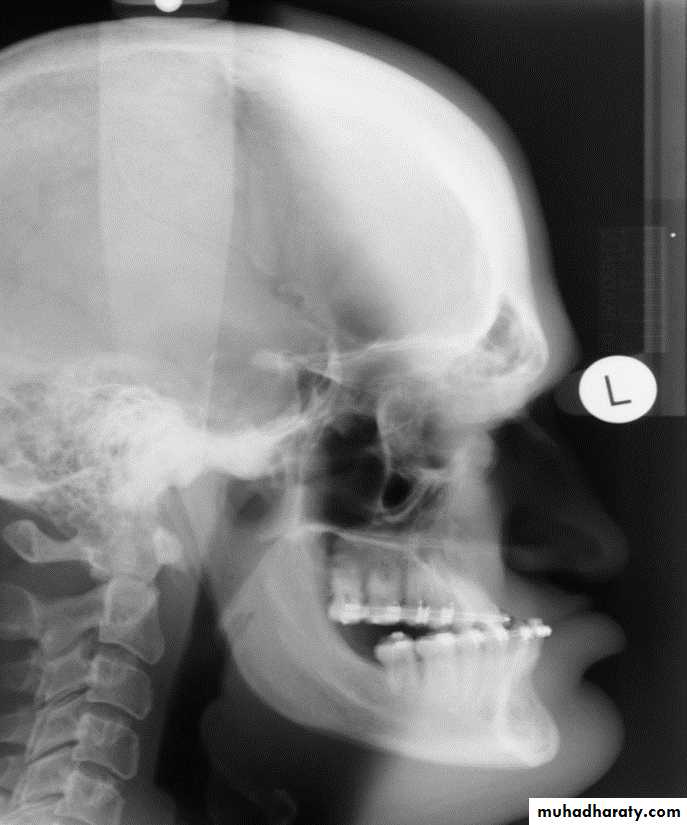

Acromegaly & prognathism

Skull manifestation of the acromegaly

1.Thickening of the skull vault &diplioc space2.Thickening of the posterior occipital tubercle

3.Prognathism

4.Froehead bossing with enlargement of the frontal sinuses also with enlargement of the mastiod air cell .

5.Balloning with Double floor appearance of the sella tursica .